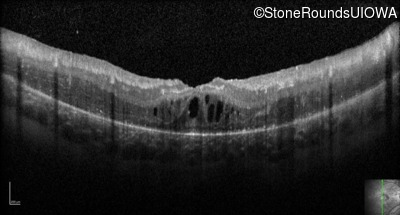

Optical Coherence Tomography - Right - 20/80 -1

Exemplar / OCT Stack